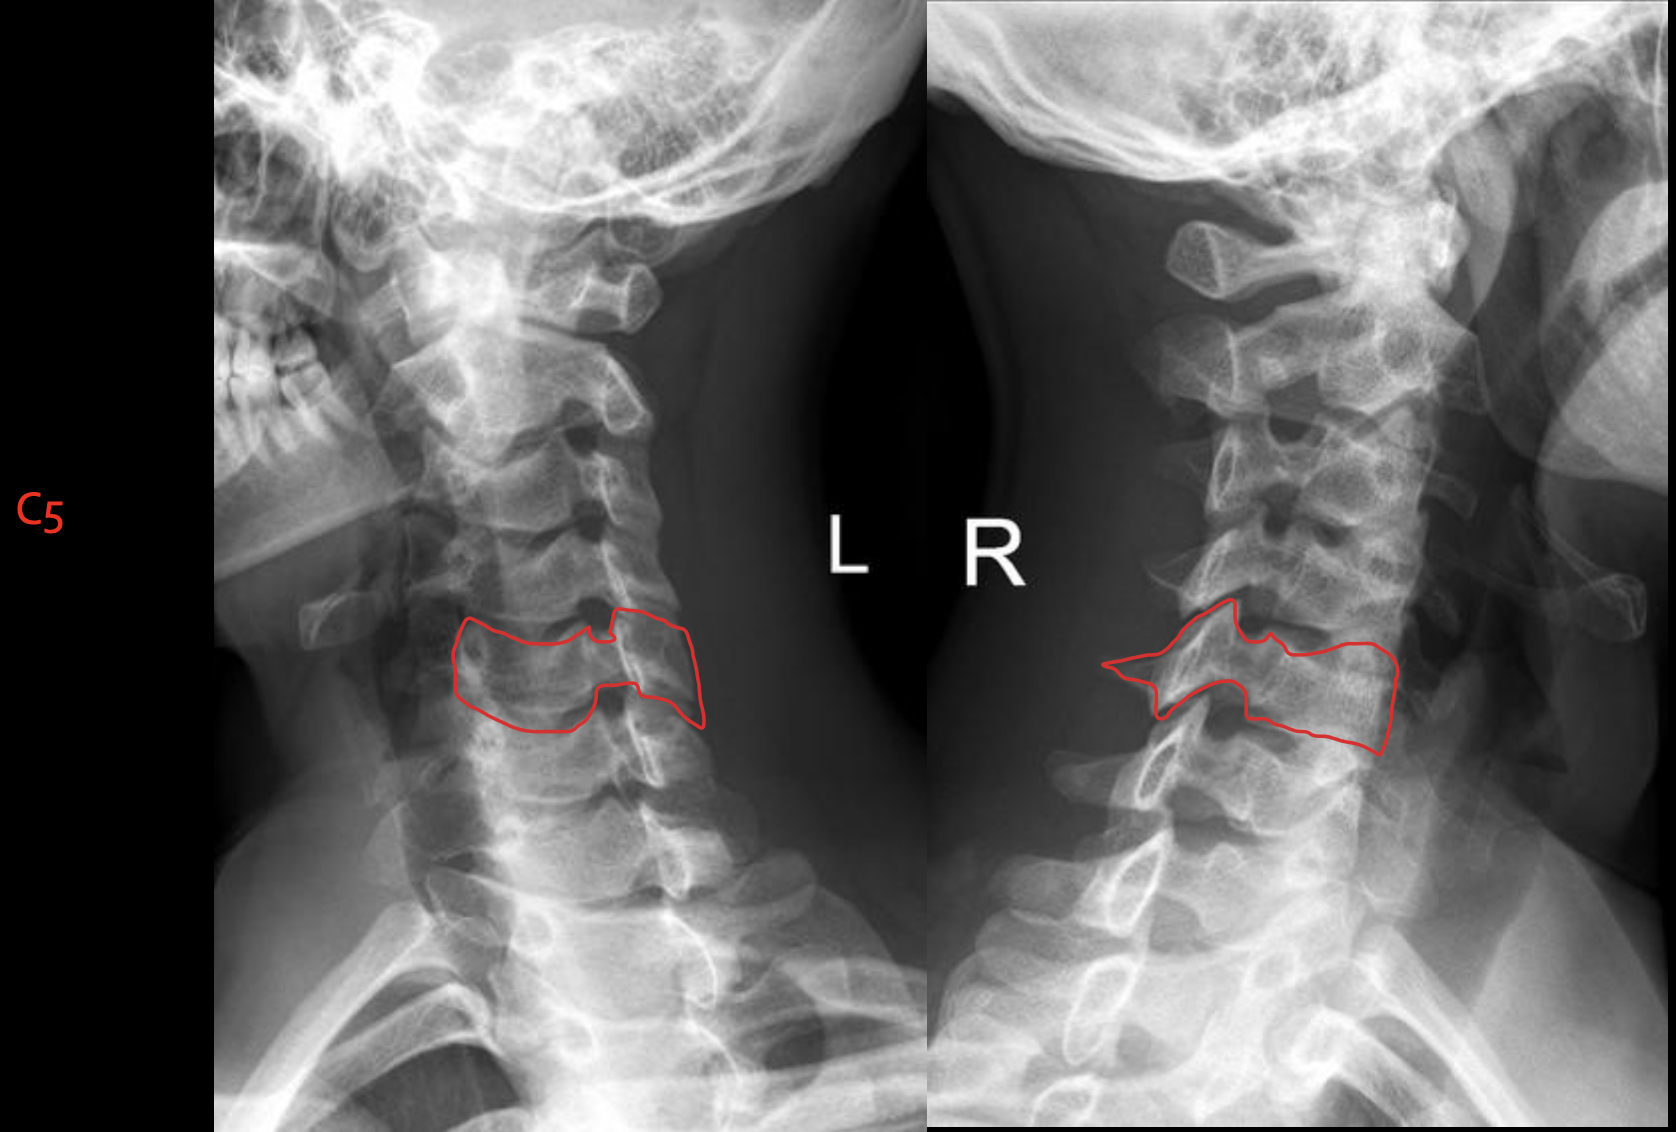

c5